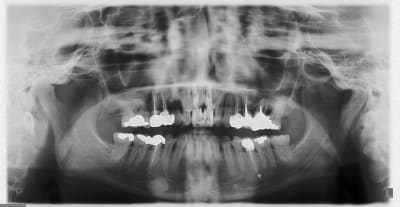

un autre cas EII MCI sur 11/21...mais en photos (j'ai aussi la vidéo, faut que je la passe sur youtube)